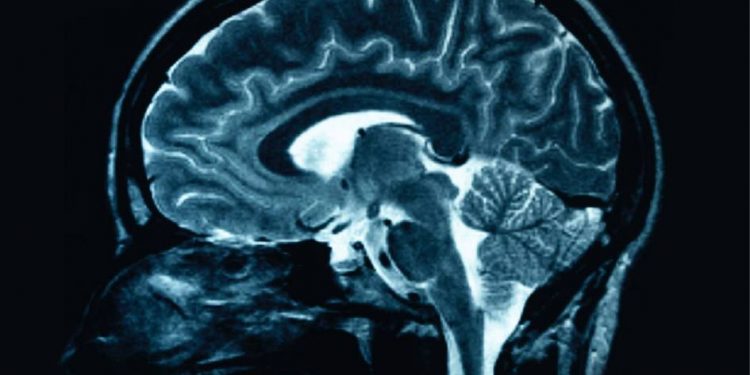

Eine führende Theorie zur „Ursache“ der Alzheimer -Erkrankung ist seit mehreren Jahrzehnten, dass sich in bestimmten Teilen des Gehirns ein toxisches Protein namens Beta -Amyloid aufbaut und die Funktion beeinträchtigt. Wenn das stimmt, sind die nächsten Fragen 1) Warum sammelt sich das Protein an und 2) was kann getan werden, um es zu verhindern.

Vorwürfe, dass ein Teil einer wichtigen Studie von 2006 zur Alzheimer -Krankheit hergestellt worden sein könnte, haben die Forschungsgemeinschaft erschüttert und die Gültigkeit der einflussreichen Ergebnisse der Studie in Frage gestellt.

Wissenschaftsmagazin Am Donnerstag sagte es, dass es Beweise dafür enthüllte, dass Bilder in der vielzitierten Studie, die vor 16 Jahren in der Zeitschrift Nature veröffentlicht wurde, möglicherweise gemocht worden sein.

Mehr als 1 Milliarde US-Greenback an staatlichen Finanzmitteln in Bezug auf die Nationwide Institutes of Well being wurden an die amyloidbedingten Alzheimer-Forschung gerichtet. Während die Untersuchung darauf hindeutet, dass Studien zu Aβ*56 für eine neue Prüfung geöffnet werden sollten, sagten Experten, die gesamte Theorie sollte nicht diskreditiert werden.